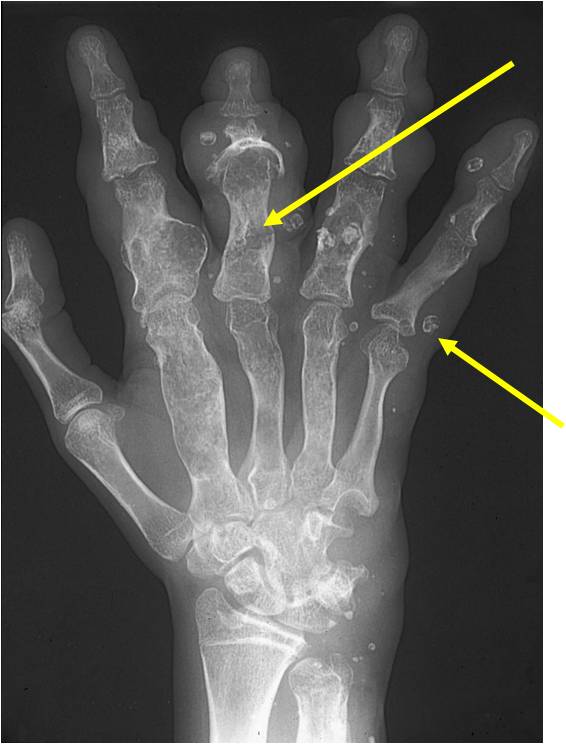

Enchondromatosis

- (Multiple Enchondromas/Ollier Disease

- Enchondromatosis is a rare disorder that is not hereditary in which the patient is afflicted with multiple intraosseous cartilaginous tumors or enchondromas.

- Usually affects the extremities

- Variable severity

- May be predominantly unilateral or affect a single extremity/limb

- Affected limb is often shortened and deformed and angulated

- May become stable at puberty

- Higher risk of malignant transformation to chondrosarcoma (5-50%) as opposed to an isolated enchondroma

- Marked skeletal deformity

Enchondromas in enchondromatosis may involve the metaphysis, diaphysis, epiphysis and articular cartilage